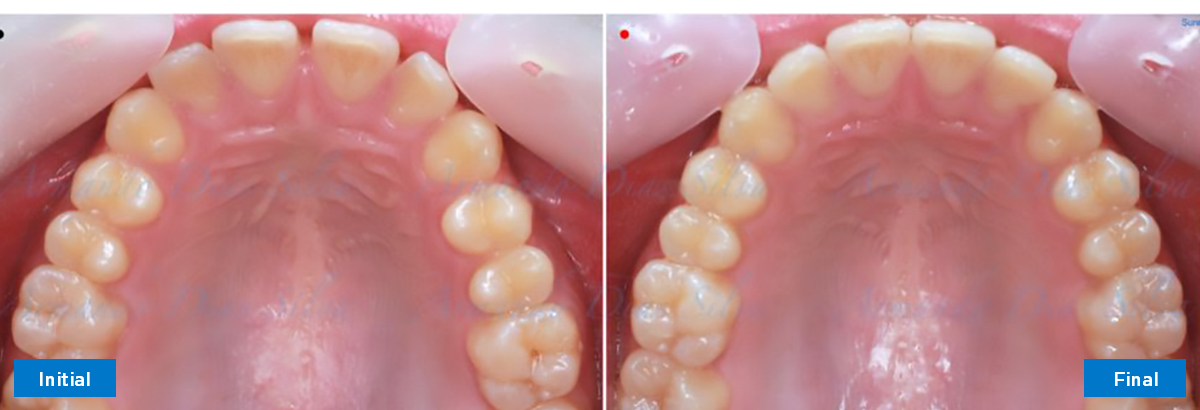

• Espaciamiento leve de las arcadas superior e inferior (deficiencia transversal de 3,45 mm)

• Deficiencia transversal maxilar leve (3,45 mm)

• Alinear y nivelar sin extracciones

• Desrotar y distalizar los molares superiores

• Retruir los incisivos superiores

• Molares de clase I logrados con distalización y sin elásticos

• Sin expansión maxilar, respetando la envoltura periodontal